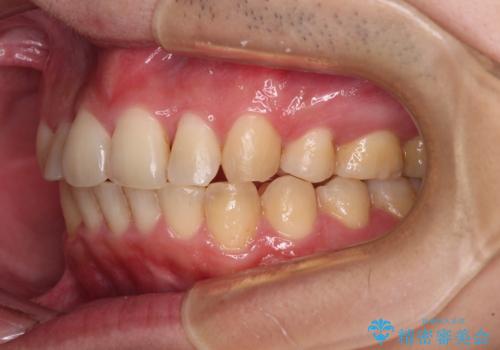

- 矯正装置

- 審美装置

- 結婚式が近いとのことで、前歯のデコボコを改善したいと来院された患者様です。

口元の突出感はないものの、上顎前歯のデコボコが著しかったため、上顎左右第一小臼歯2本を抜歯することとしました。

咬合力が非常に強く、抜歯したスペースがなかなか閉じないであろうことは予想できましたが、思っていた以上に期間がかかりました。

前歯のすり減りも著しかったため、仕上げの位置の調整にも期間を要しました。